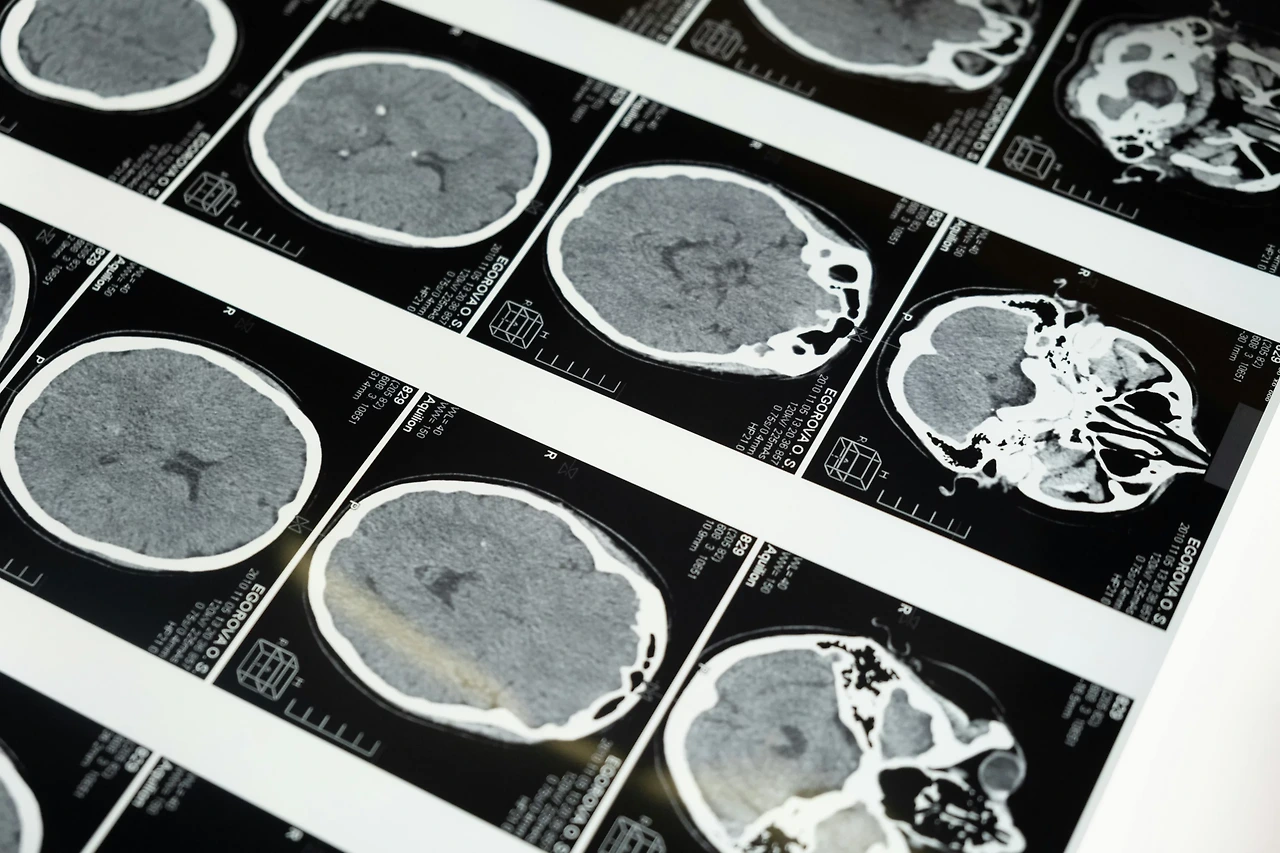

2. 뇌경색 검사

뇌경색이 의심되는 상황에서는 가능한 한 빠르게 정확한 검사가 이루어져야 합니다.

병원에서는 먼저 CT를 촬영해 뇌출혈 여부를 확인하고, 이어서 MRI나 MRA를 통해 혈관이 어느 부위에서 막혔는지 정밀하게 파악합니다.

MRI는 초기 뇌경색까지도 민감하게 확인할 수 있어, 발병 초기에 큰 도움이 됩니다.

또한 경동맥 초음파를 통해 목 혈관의 좁아짐이나 혈전 여부를 평가하는데, 이는 중장년층에게 특히 중요한 검사입니다.

심전도나 심장 초음파도 함께 시행하는데, 심방세동이나 심장 질환이 뇌경색의 주요 원인이 되는 경우가 많기 때문입니다.

혈액검사도 진행하여 당뇨, 콜레스테롤, 염증 지표 등을 확인하며 위험 요인을 종합적으로 파악합니다.

때로는 혈관 조영술을 통해 막힌 혈관을 시각적으로 확인해야 하는 경우도 있습니다.

검사 과정이 복잡해 보일 수 있지만, 각각의 검사는 뇌경색을 정확히 판단하고 치료방향을 결정하는 데 꼭 필요한 과정입니다.

무엇보다 시간 안에 검사를 해야 치료 선택지가 넓어지기 때문에, 의심되는 증상이 나타나면 즉시 병원을 찾는 것이 가장 중요합니다.